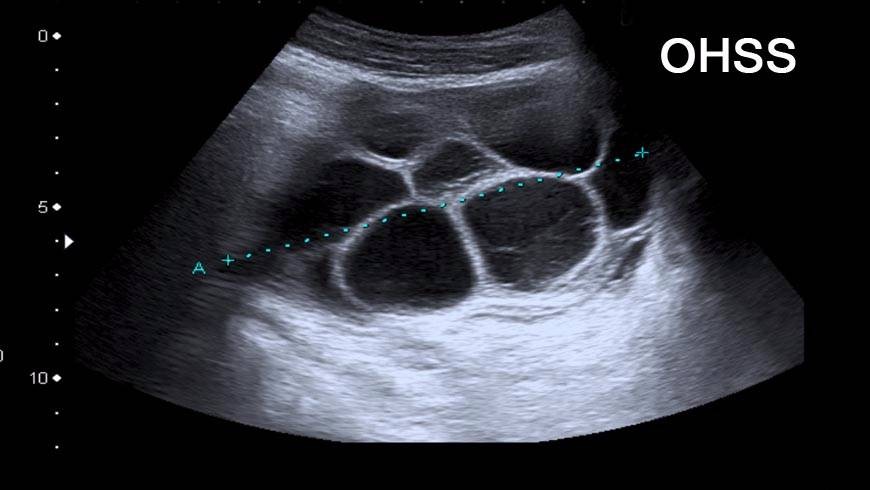

ПовечеСиндром на яйчниковата хиперстимулация

Публикувано на: 23.02.2008 Синдромът на яйчниковата хиперстимулация (Ovarian hyperstimulation syndrome - OHSS) е свръхреакция к...